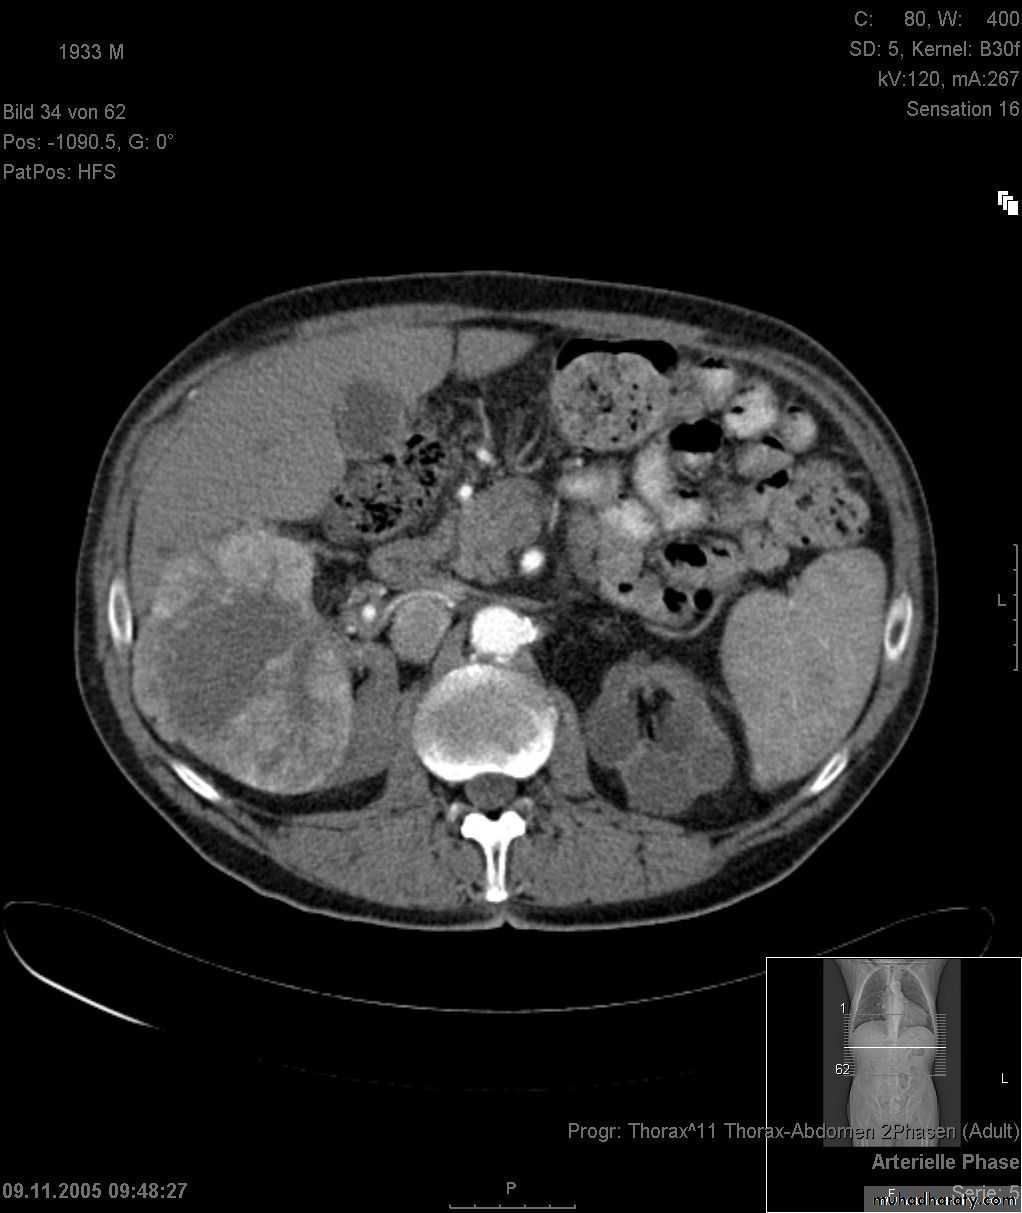

RENAL TUMOR Adenocarcinoma ( Hyper nephroma)

* Comprise 80% of renal malignant tumor. next epithelial T. of renal pelvis (transitional cell Ca.) ; Nephroblastoma ( Wilm’s Tumor ).* Clinically may be silent or presented with loin pain , heamaturia and loin mass .

* Usually unilateral , rare bilateral .

KUB :-

* Soft tissue mass.

* Bulging in renal out-line .

* Diffuse renal enlargement .

* Calcification occur in 6 % of cases .

IVU :-

* Nephrogram shows filling defect which is irregular .* Distracted PCS .

* Hydronephrosis.

* Amputation & missing calyces .

* Large non-functioning kidney .

Angiogram

US

CT

MRI